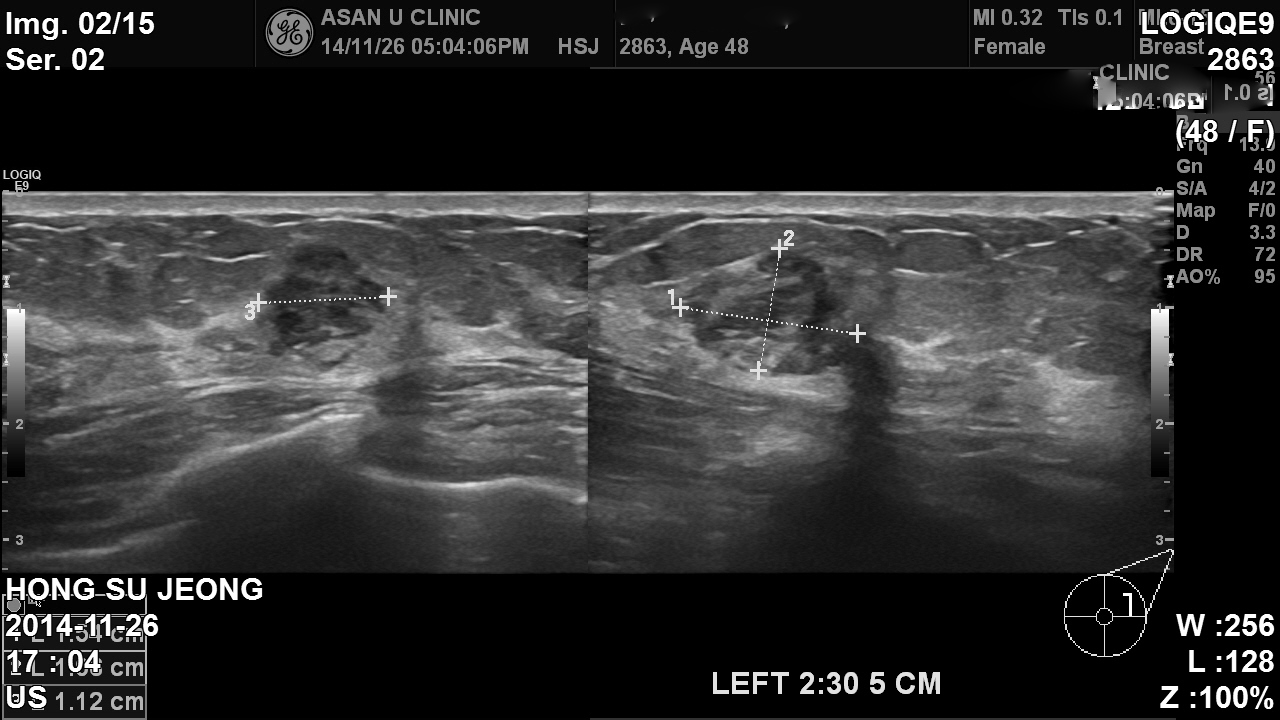

건강검진상 이상소견으로 내원한 48세 여성분입니다.

좌측 유방 상외측에 1.3cm의 혹이 있었고 진찰 상 좌측 겨드랑이에도 림프절의 비대가 있었습니다.

조직검사를 시행하여 좌측유방의 혹과 겨드랑이 림프절비대부를 조사하여

좌측유방의 침윤성 유관암과 액와림프절 전이암으로 진단되었습니다.